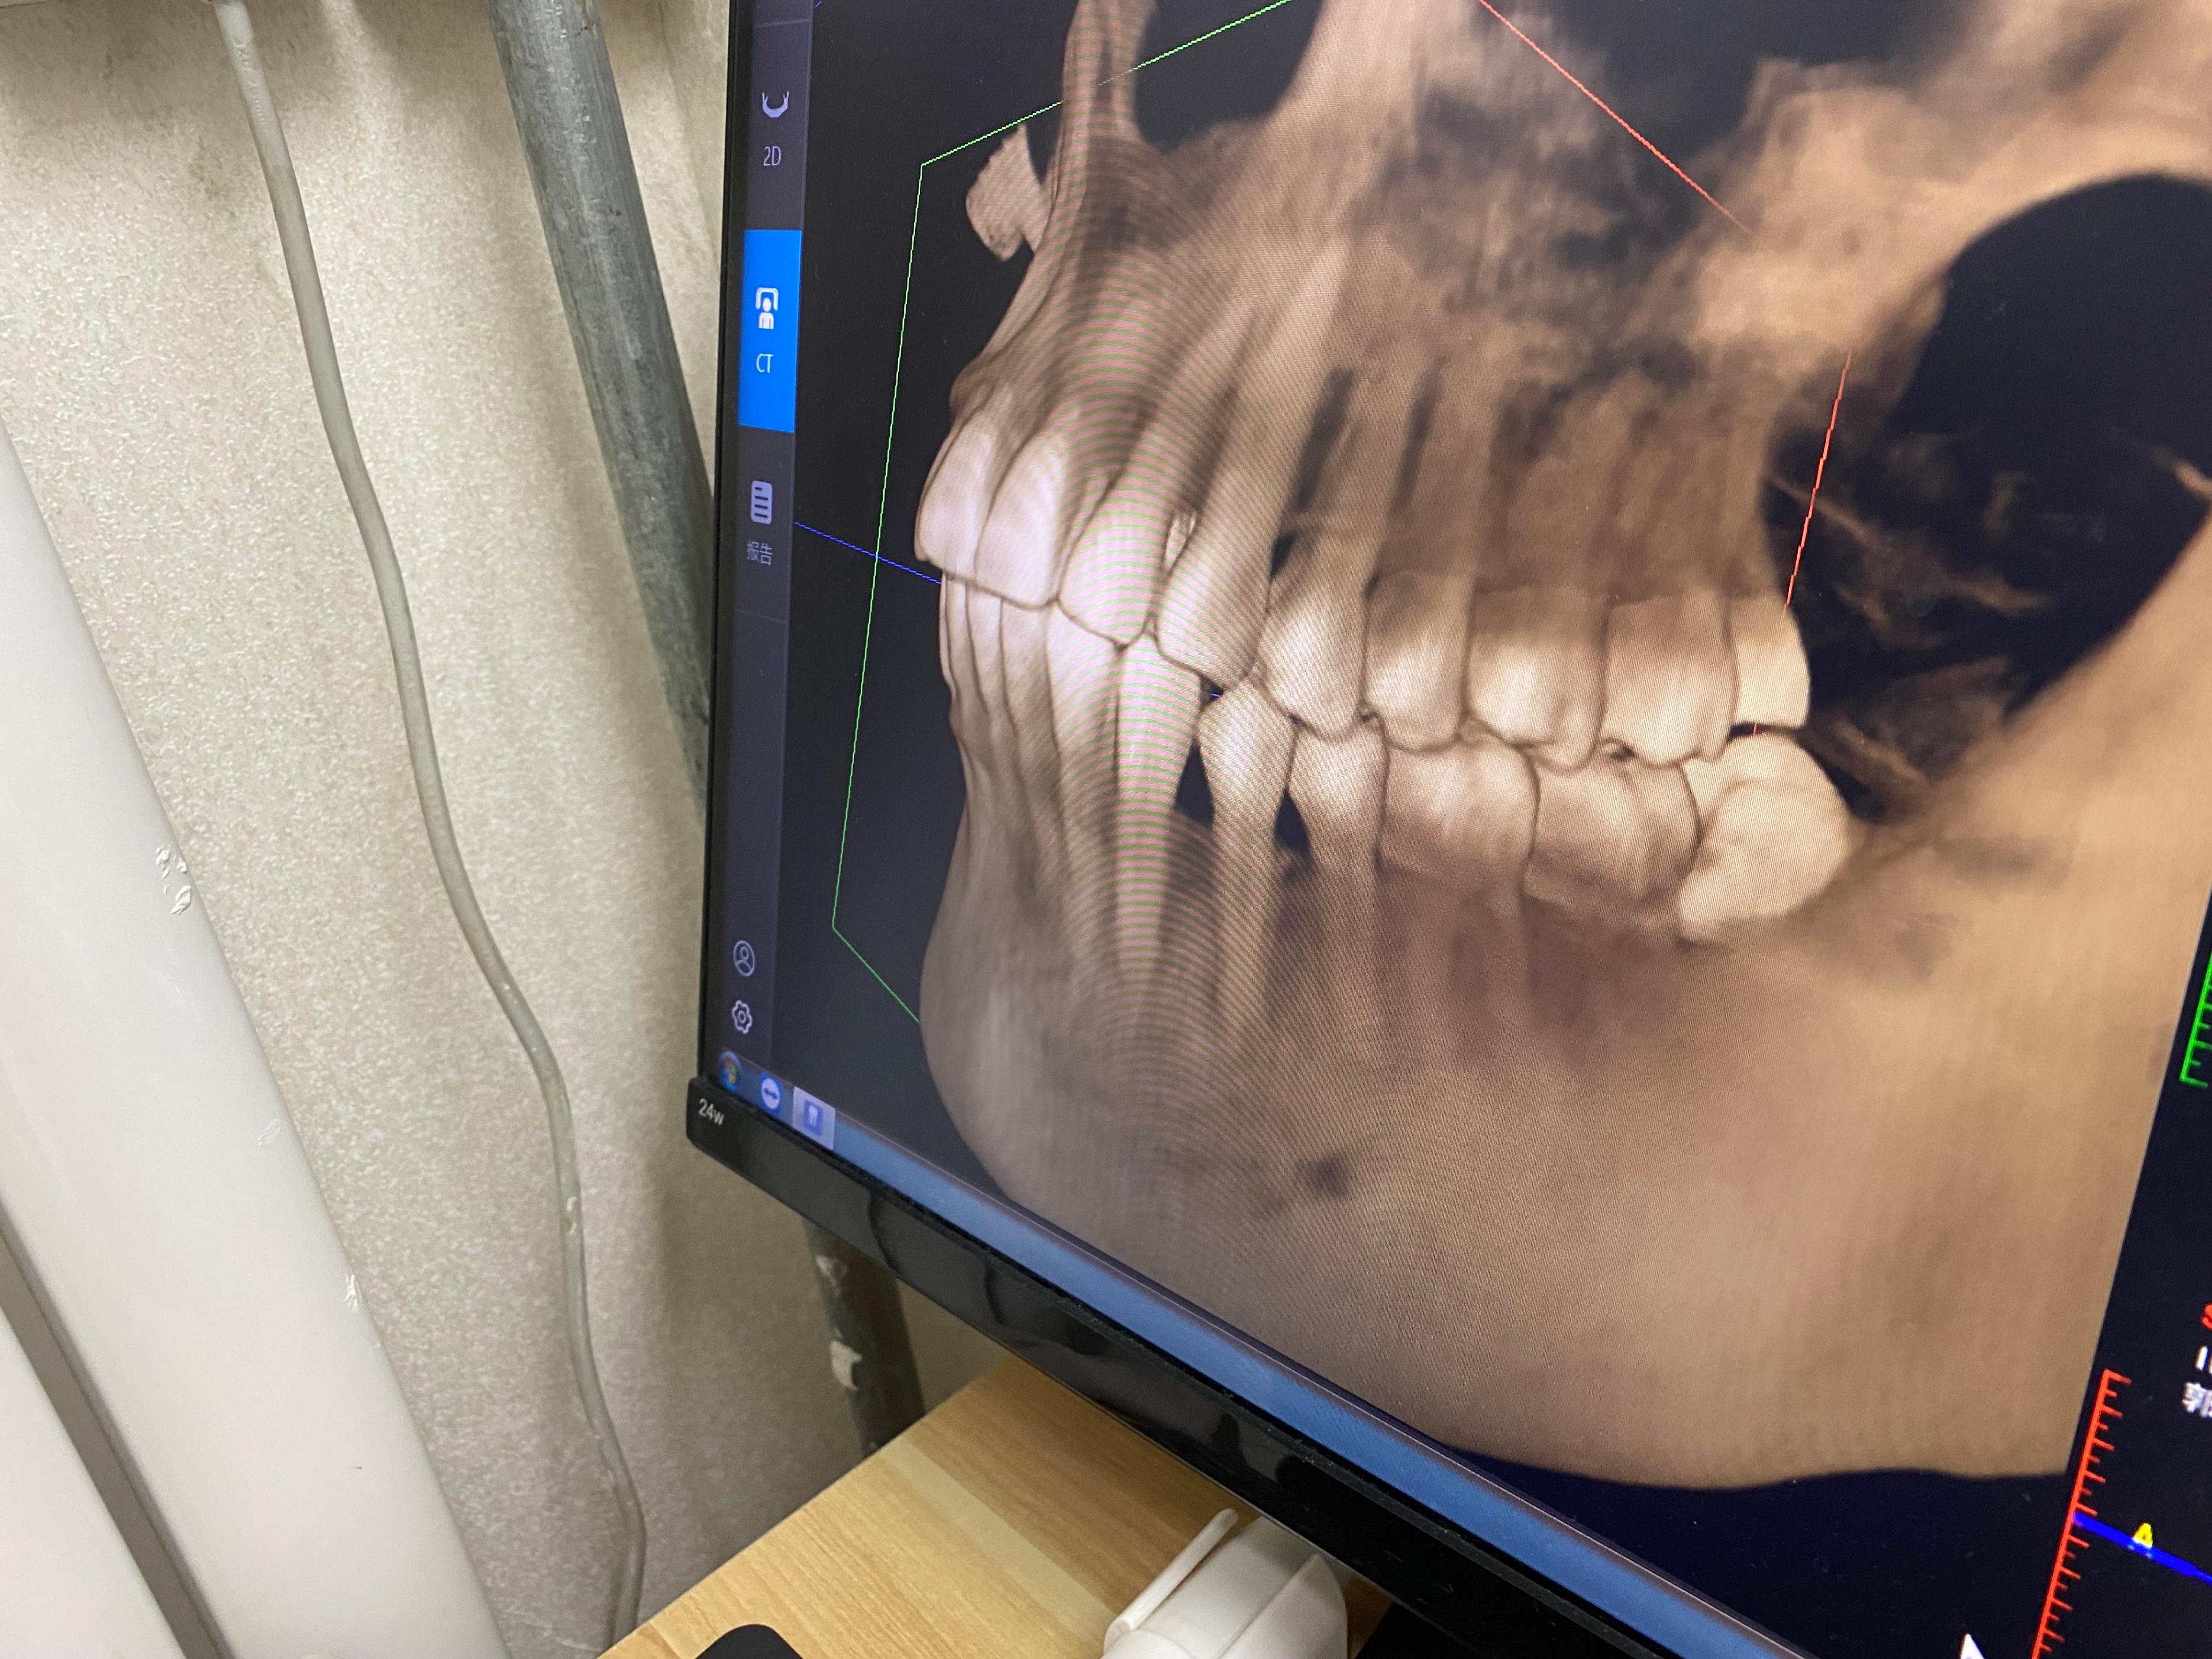

洗完牙,拍了照片,发现了我的四颗智齿,医生建议全部拔掉,从照片上来看,有颗确实长歪了,把前面的牙齿都顶了个洞。

先拍了照片,医生说先拔左侧的智齿,它把前面的牙弄坏了,比较着急。

拔智齿,真的特别特别疼,我左下侧的智齿是阻生齿,斜着长的,先打了麻药,医生试了试,说不能直接拔,需要切开牙龈,把牙齿切成2瓣,再一个个个取出。